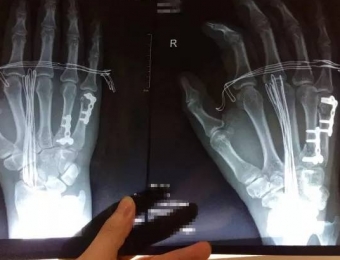

装了钢板,一定要取吗?RELEASE:2017-10-19 SEE:0

当骨折损伤严重、断端极其不稳定时,打石膏、支具这种外固定方式可能会引起骨折再移位。这时,骨科医生一般都会建议患者使用内固定的方式,也就是常说的装钢板。